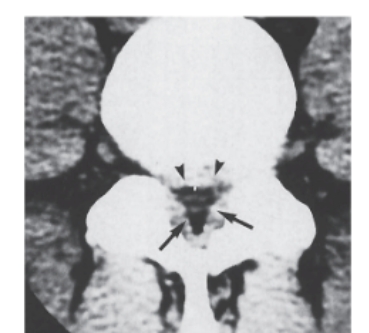

10

-Refer to the figure. Name the image and pathological condition.

A) Sagittal MRI, stenosis

B) Axial MRI, vertebral compression

C) Sagittal CT, spondylolisthesis

D) Axial CT, stenosis